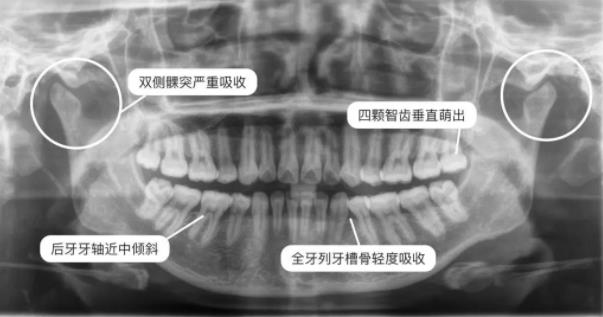

全景片裏可以看出很多牙齒問題

拍全景片通常是為(wei) 了了解全口牙齒數量、有無多生牙、埋伏牙,牙根有無吸收、牙齒位置好不好,還有牙槽骨和牙周的情況怎麽(me) 樣等,便於(yu) 提前處理。有人說,如果整牙前不拍全景片,就是醫生自己在給自己埋炸彈,也是不負責任的做法。